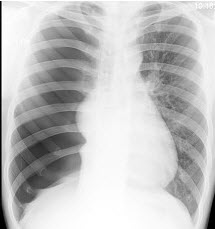

22、单项选择题

根据图像,最可能的诊断是()

A.肺气肿

B.慢性支气管炎

C.气胸

D.纵隔气肿

E.肺转移瘤